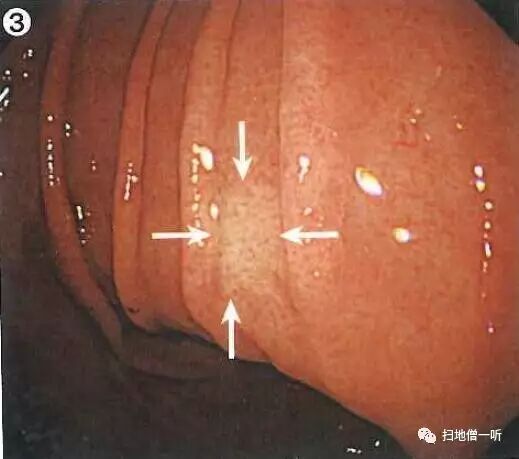

背景粘膜为c-3型萎缩表现,胃窦可见多发红斑,胃窦小弯侧可见一边缘微隆起中央发红的凹陷型病变

递近观察凹陷面周边微隆起更加明显

靛胭脂染色后可见凹陷边界呈棘状蚕食像,结合边缘反应性隆起,考虑分化型癌

最终病理诊断:

胃窦小弯,O-IIc,10mm,tub1,T1a (M),UL(-)

病例小结:

• 发红凹陷伴周围隆起型病变多考虑分化型癌

• 靛胭脂染色有助于观察蚕食像

其他图片解读:

胃角小弯可见一不规则型糜烂灶,边界呈棘状蚕食像

活检结果为Group1

针对内镜下有疑虑的病变,应该积极行病理活检